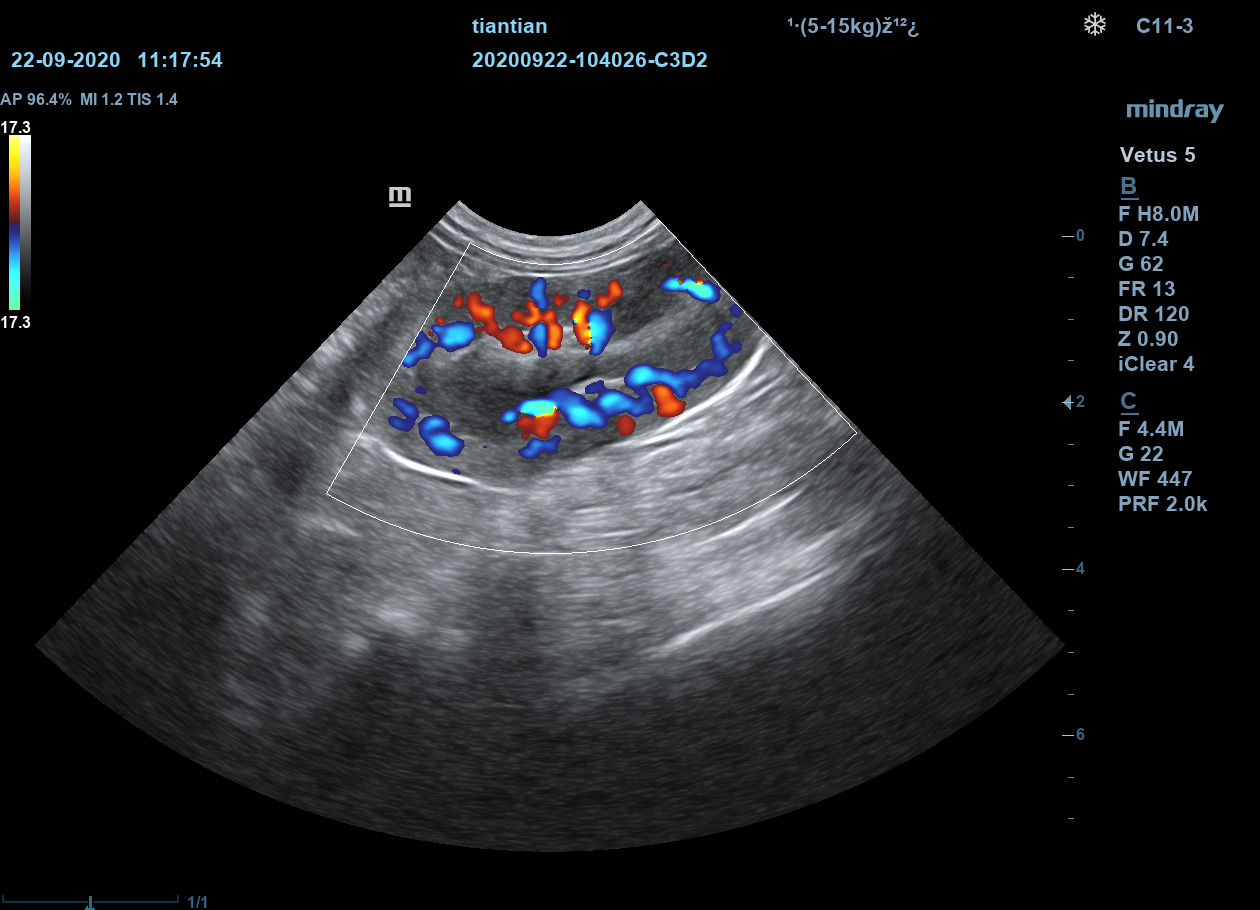

Ветеринарный ультразвуковой аппарат Mindray Vetus 5 использует новейшие технологии и ПО и позволяет проводить скрининг внутренних органов животных, получая чёткие и достоверные данные об их структуре, размерах и расположении.

Позволяет получать УЗИ-изображения с учётом анатомических особенностей животных.

Подразделяет животных по размеру и весу для максимально точной диагностики.

iTouch

Автоматическая оптимизация изображения. При помощи одной кнопки врач узи диагностики получает автоматическую настройку необходимых параметров для улучшения визуализации исследуемого объекта. Оптимизация изображения работает как в B-режиме, так и в режимах ЦДК, ЭДК и PW.

iTouch

Автоматическая оптимизация изображения. При помощи одной кнопки врач узи диагностики получает автоматическую настройку необходимых параметров для улучшения визуализации исследуемого объекта. Оптимизация изображения работает как в B-режиме, так и в режимах ЦДК, ЭДК и PW.